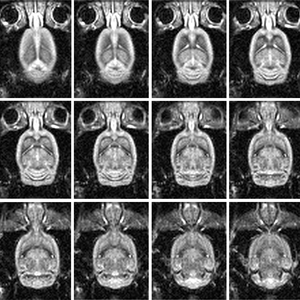

A sample high-resolution dataset